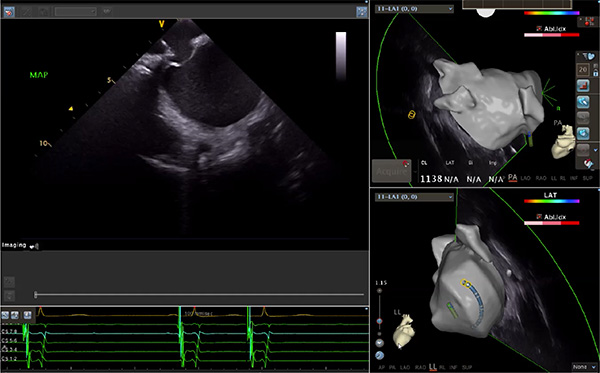

超聲心動(dòng)圖技術(shù)包括常規(guī)經(jīng)胸超聲(TTE)、經(jīng)食管超聲(TEE)、心腔內(nèi)超聲(ICE)、超聲聲學(xué)造影(MCE)、三維超聲心動(dòng)圖等,ICE是一種新興技術(shù)——將微型的換能器安裝在心導(dǎo)管的尖端,經(jīng)由外周血管輸送至心腔內(nèi)部,換能器發(fā)射聲波,對(duì)心臟及其鄰近組織進(jìn)行實(shí)時(shí)高質(zhì)量成像和(或)血流動(dòng)力學(xué)測(cè)定的超聲成像技術(shù)?;诓煌募夹g(shù)原理,心腔內(nèi)超聲導(dǎo)管被分為兩類:機(jī)械旋轉(zhuǎn)式超聲導(dǎo)管和相控陣超聲導(dǎo)管。目前,臨床上主要應(yīng)用的是相控陣超聲導(dǎo)管,ICE成像通過術(shù)者旋轉(zhuǎn)導(dǎo)管及操縱導(dǎo)管手柄上的兩個(gè)旋鈕來完成。

ICE門檻高、集成了超聲和圖像處理最前端的技術(shù),是當(dāng)前內(nèi)窺超聲方向最挑戰(zhàn)的領(lǐng)域。不同于傳統(tǒng)接觸式三維重建方法會(huì)產(chǎn)生假腔,影響術(shù)者對(duì)靶點(diǎn)或結(jié)構(gòu)的判斷,心腔內(nèi)超聲(ICE)可直接顯示心臟結(jié)構(gòu),有助于理解心臟內(nèi)各部位之間的解剖關(guān)系,不僅具有實(shí)時(shí)成像、并發(fā)癥監(jiān)測(cè)以及良好的耐受性,同時(shí)以股靜脈入路,無需全麻或深度鎮(zhèn)靜,日益成為心臟介入手術(shù)中重要輔助工具,被譽(yù)為心臟介入醫(yī)生的“黃金眼”。心腔內(nèi)超聲可用于多種心臟介入手術(shù),潛在患者群體龐大,動(dòng)脈網(wǎng)測(cè)算我國心腔內(nèi)超聲導(dǎo)管市場空間或?qū)⒊?00億元,具有廣闊前景。

隨著心腔內(nèi)超聲的應(yīng)用更廣,性能也在逐漸優(yōu)化,已從二維成像轉(zhuǎn)變?yōu)?strong>三維成像,極大增強(qiáng)了引導(dǎo)及可視化能力。二維心腔內(nèi)超聲支持雙平面或三平面成像,可顯示兩個(gè)或三個(gè)不同的平面視圖,但醫(yī)生需將這些圖像在腦海中重新構(gòu)建為三維解剖結(jié)構(gòu)。三維心腔內(nèi)超聲則可直接呈現(xiàn)三維解剖結(jié)構(gòu)圖,便于醫(yī)生更輕松地開展手術(shù)。按照產(chǎn)品發(fā)展方向,預(yù)計(jì)心腔內(nèi)超聲還將向更清晰、精準(zhǔn)、多功能等方向發(fā)展。